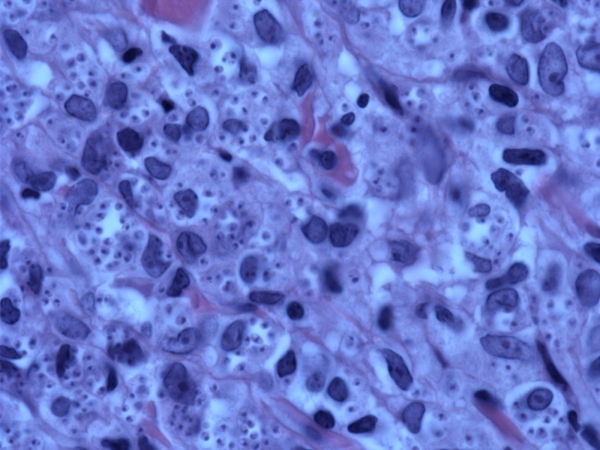

Leishmaniasis: Three main types: cutaneous (L tropica and mexicana), mucocutaneous (L. brasiliensis) and visceral/kala-azar (L donovani). Old world Leishmania (L tropica-major, minor and aethiopica) transmitted by Phlebotomus sandfly, new world (L mexicana, brasiliensis) transmitted by Lutzomyia sandfly. The promastigote lies in the sandfly is transmitted to humans and the amastigote infects macrophages. Macrophages become engorged with the organisms, but there is abnormal intracellular killing. Histology: Epidermis may display PEH and there is a dense dermal infiltrate consisting of foamy histiocytes, aka Leishman-Donovan bodies, with intracellular amastigotes along with epithelioid monocytes, giant cells, plasma cells and lymphocytes, variable eosinophils and PMNs. Organisms stain better with Giemsa, have a paranuclear kinetoplast and typically are located at periphery of macrophage, i.e. the Marquee sign. Can also see organism on skin slit smear. Older lesions show decreased organisms and tuberculoid granulomas may form.

Fig 4 Leishmaniasis. Very high-power view showing amastigotes surrounded by a clear space.